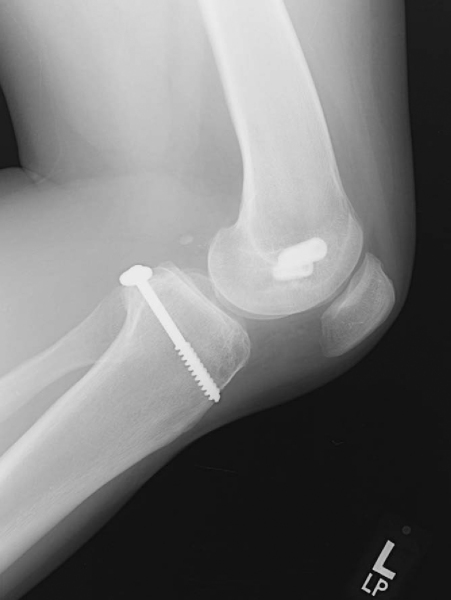

On physical examination, it is important to assess the neurovascular status of the injured limb. This is especially important if there is a history of a knee dislocation, which has a higher risk of such an injury. Inspection and palpation for an effusion is followed by assessment of the range of motion. With the knee in a flexed position, palpate for the natural tibial step-off and evaluate the anterior border of the tibial plateau in relation to the femoral condyles. In addition, a Godfrey test can be performed, whereby the lower leg is elevated with the knee flexed approximately 90 degrees to assess for the presence of a “sag.” A posterior drawer test with the knee in 90 degrees of flexion is also performed to evaluate the amount of posterior tibial translation (

Fig. 67-1

). It is important to recognize the presence of a posterolateral corner knee injury, which is commonly associated with a PCL injury and will accentuate the posterior drawer.[13] The gait pattern is inspected for any varus thrust. If a posterolateral corner injury is suspected, the physical examination should include a reverse pivot shift test, a dial test, a posterolateral drawer test, and varus stress testing at both 30 degrees and 90 degrees.